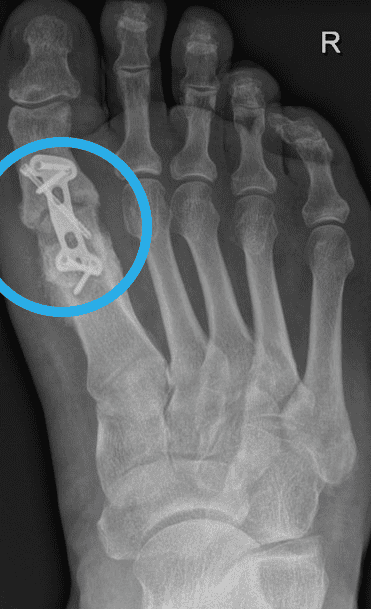

Was ist eine Pseudarthrose? Wenn es 6 Monate nach einem Bruch nicht zur Heilung des Knochens gekommen ist, spricht man laut Definition von einer Pseudarthrose. Zur Heilung werden bei Operationen in der Regel Schrauben aus menschlichem Knochen verwendet. Das Wort Pseudarthrose stammt aus dem Griechischen, wobei „pseudos“ falsch bedeutet und „arthros“ Gelenk. Eine Pseudarthrose ist auch unter den Namen Pseudogelenk oder Scheingelenk bekannt. Pseudarthrosen treten immer nach einem Knochenbruch oder einer Knochenoperation auf, wenn der Knochen nicht richtig verheilt, die Knochenstücke nicht zusammenwachsen. Solange der Knochen nicht vollständig geheilt ist, kann er auch nicht richtig belastet werden. „Auslöser einer nicht heilenden Fraktur ist meist eine zu frühe Belastung, aber auch Entzündungen und Infektionen können den Knochenheilungsprozess einschränken. Der Knochen wächst nach einem Bruch nicht zusammen und in der Folge entsteht die Pseudarthrose.“ So der Experte aus Linz, Dr. Klaus Pastl. Pseudarthrosen können an jedem Knochen, der nicht verheilt, auftreten, egal ob es sich um eine nicht heilende Mittelfuß- Operation, eine fehlgeschlagene Hallux rigidus Operation oder eine nicht heilende Operation nach einem Kahnbeinbruch handelt. Tritt eine Pseudarthrose auf, muss diese behandelt werden.

Symptome einer Pseudarthrose

Ein eindeutiges Anzeichen einer Pseudarthrose ist, wenn die Knochenbruchenden innerhalb von 4 – 6 Monaten nicht stabil zusammengewachsen sind. Weitere typische Symptome einer Pseudarthrose sind Rötungen, Schmerzen und Schwellungen über dem nicht geheilten Knochenbereich. „Da durch die Pseudarthrose die Stabilität des Knochens stark beeinträchtig ist, treten häufig Fehlstellungen, Bewegungseinschränkungen, Gelenksprobleme aber auch Muskelschwund in der betroffenen Region auf.“, erklärt Dr. Klaus Pastl, Orthopäde aus Linz. Bei den meisten Betroffenen treten Schmerzen anfangs nur bei Bewegung und Belastung auf. Schreitet die Pseudarthrose fort, treten die Schmerzen und Symptome aber auch in der Ruhephase auf. Tritt eine Pseudarthrose nach einer Implantation von Metallschrauben oder Metallplatten auf, ist ein zu spätes Reagieren besonders gefährlich. Heilt der Knochen nicht rechtzeitig, lastet das gesamte Gewicht auf den Metallplatten und Metallschrauben. Diese können durch die Belastung brechen. „Gebrochene Metallteile im Körper können äußerst schmerzhaft für Patienten sein. Auch für den Chirurgen sind diese Operationen äußerst unangenehm und schwierig. „Operationen sind mühsam und komplex. Oft muss viel Knochen zerstört und die umgebenden Weichteile verletzt werden, um die gebrochenen Metallteile aus dem Knochen des Patienten zu bergen. Manchmal können nicht alle Metallteile entfernt werden und müssen dann im Knochen verbleiben. Das ist frustrierend, für Patienten und Chirurgen.“

Die Behandlung einer Pseudarthrose kann ein langwieriger Prozess sein und kann sich oft über Monate ziehen. Meist kommt zur erfolgreichen Behandlung einer Pseudarthrose nur eine Operation in Frage. Gute Chancen auf eine Heilung haben Patienten, die mit Schrauben aus menschlichem Knochen versorgt werden.

Die Pseudarthrose Operation

Eine Pseudarthrose Operation ist unbedingt erforderlich, wenn konservative Therapien nicht die gewünschten Ergebnisse bringen und die Schmerzen weiterhin bestehen. In der Folge sind mögliche Pseudarthrose Operationen aufgelistet:

- Einbringen von Spenderknochen (Allograft) in den Bruchspalt:

- Hierbei handelt es sich um Allografts und Schrauben aus menschlichem Knochen wie der Shark Screw®.

- Knochenverbindende, Osteosynthese

- Als Osteosynthesematerial werden in der Regel Schrauben aus menschlichem Knochen Bei Pseudarthrosen an großen Röhrenknochen, können diese als Ergänzung zu bestehenden Plattensystemen eingesetzt werden.

Kann die Shark Screw® helfen eine Pseudarthrose zu heilen?

„Ich selbst setze Shark Screw® bei der operativen Versorgung meiner Patienten mit Pseudarthrosen sehr erfolgreich ein! Also ja, mit Shark Screw® hat man eine gute Chance Pseudarthrosen zuheilen.“ so der Pseudarthrose Spezialist Dr. Klaus Pastl aus Österreich. Aber warum eignet sich Shark Screw® gerade für Pseudarthrosen gut? Shark Screw® wird nach dem Einbringen in den Knochen von körpereigenen Zellen besiedelt, durchwachsen und dabei in den natürlichen Knochenumbauprozess integriert. Grund dafür sind die sogenannten Havers-Kanäle, die sich im Inneren der Shark Screw® befinden. „Shark Screw® dient bei Pseudarthrosen als Leitsubstanz und Brücke für körpereigene Zellen. In diesen Kanälen können sich körpereigene Gefäße und Knochenzellen ansiedeln und ausbreiten.3 Durch diesen Vorgang entstehen neue Knochenstrukturen, deren Neubildung gerade bei Pseudarthrosen essenziell sind, um diese zu heilen.